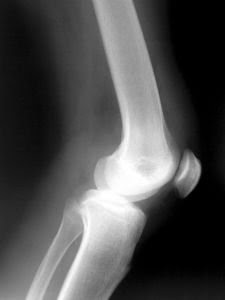

As a matter of fact, what’s cracking but not causing pain is known as Crepitus. It’s said to be air being trapped on the joints space due to cartilage wear. It does not only happens to the knee, it also happens to other joints of the body.